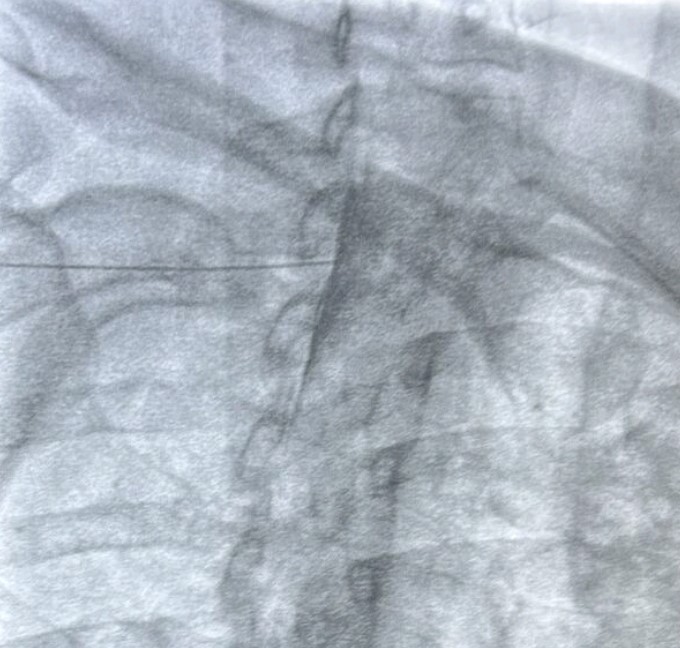

- Κατάλυση των αυχενικών αρθρώσεων με χρήση ραδιοσυχνοτήτων

- Επισκληρίδια έγχυση επί υποκείμενης κήλης μεσοσπονδυλίου δίσκου με ή χωρίς ριζιτική προσβολή